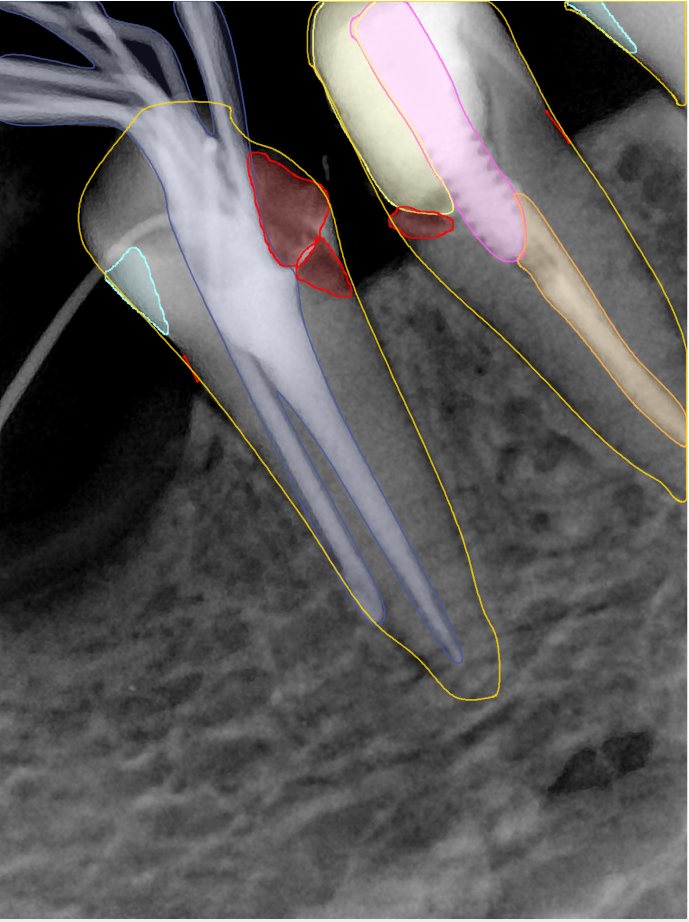

CR/DR 牙齿分割阶段记录

当前进展

- 完成了 CR/DR 牙齿相关分割训练

- 当前结果已经达到阶段预期,但仍有细节问题需要继续处理

相关测试

遇到的问题

- 训练过程中出现过 mask 下移问题

- 部分结果会出现 box 填充异常

- mask 边缘仍然有比较明显的锯齿感

参考

第二版算法问题测试